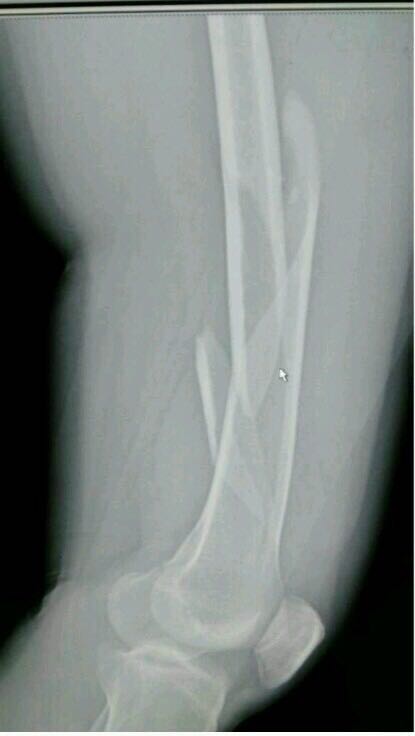

股骨干骨折

( fracture of femoral shaft;fracture ofthe shaft ofthe femur )

患者,男,30岁,股骨干骨折,撞击伤